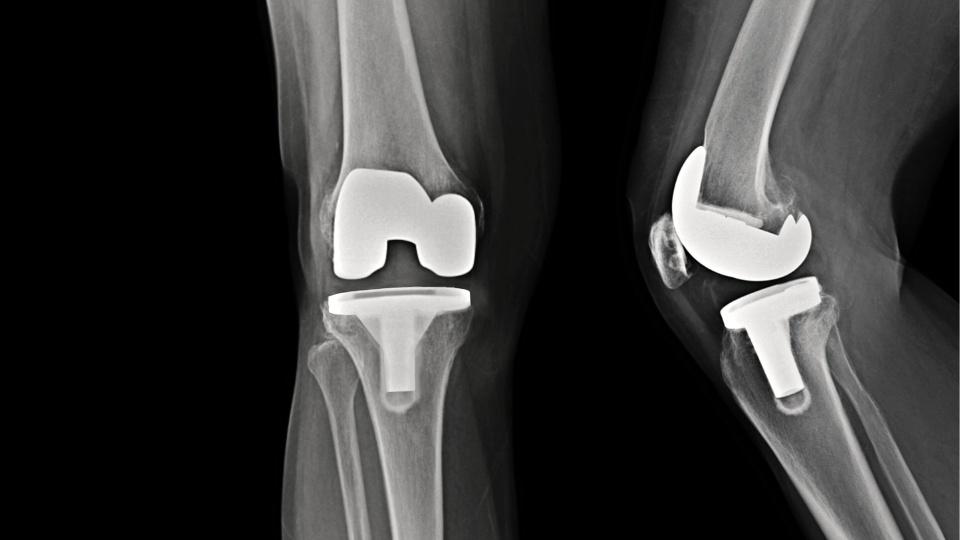

Knee Replacement

For severe knee damage and osteoarthritis, a total or partial knee replacement may be the best solution.

Dr. Mehta provides expert care using the latest approaches for a smooth recovery.